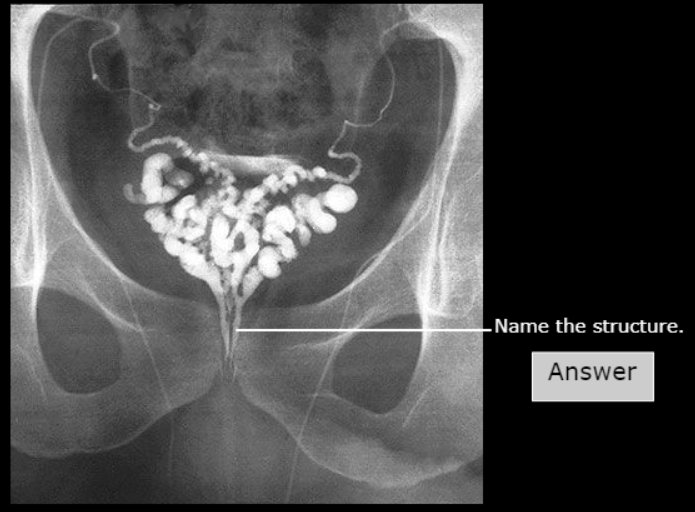

Pubic Symphysis